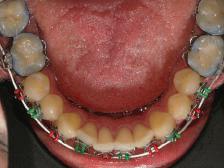

21Dental Tribune Bulgarian Edition / октомври 2022 г. ДИАГНОСТИЧНИ РЕЗУЛТАТИ: 1. Възраст на пациента: 21 години 2. Скелетен клас III (ANB 0) 3. Зъбен клас 3 4. Ръбцова захапка във фронта, кръстосана в дисталните участъци 5. Тясна горна челюст 6. Overjet – 0 мм, Overbite – 0 мм 7. Несъответствие на горната с долната средна линия 8. Единични контакти в ЦО 9. Хиподивергентен тип на растеж SN/MP – 33.5 10. Неравен гингивален контур 11. Неравна линия на усмивката 12. Тенденция за рецесии в долен фронт ПРЕПОРЪЧИТЕЛНО ЛЕЧЕНИЕ: Пълно ортодонтско лечение с метални брекети „Алекзандър“ Корекция на клас 3 захапката в областта на кучешките зъби с екстракция на първите пре молари в долна челюст Корекция на кръстосаната захапка в дистални участъци Коригиране на ръбцовата захапка във фронта Подобряване на ОJ и OB на пациента Стрипинг в долен фронт Подреждане на зъбите в горната и долната челюст Професионално хигиенизиране и профилактични дентални прегледи са препоръчителни на всеки 6 месеца. 1-ви месец След 1 месец са залепени брекети в горната челюст – поставена е еластична дъга. 016 NiTi. В долната челюст са елиминирани ротациите, поставена е стоманена дъга. 016SS, закалена с ток, и еластична верижка за затваряне на пространствата. 3-ти месец В долната челюст е поставена трета дъга – 17 x 25 NiTi с къси лигатури и верижка

В горната челюст се затварят пространствата с дъга .016SS и верижка. 5-и месец На 5-ия месец след залепяне на брекетите в долната челюст е поставена стоманена дъга 16 x 22 SS с четвъртито сечение, омега луп и тай бек. В горната челюст е поставена дъга 17 x 25 NiTi. Поради липсата на стабилни оклузални контакти са поставени лингвални верижки в областта на моларите, за да се предотврати нежелана ротация на 7-ите зъби. 6-и месец На 6-ия месец от началото на лечението са екстрахирани долните първи премолари, поставена е дъга 16 x 22 SS със затваряща чупка teardrop. Чупката се активира всеки месец по 1 мм с чинч-бек. клиничен случай | ортодонтия СТЪПКИ НА ЛЕЧЕНИЕТО Начало на лечението Лечението започва с поставяне на апарат за бърза експанзия в горната челюст. През първия месец от лечението са направени 24 оборота на апарата за експанзия. Залепени са брекети в долната челюст, поставена е дъга 17x25 CuNiTi, като са предпи сани клас 3 ластици (1/4”,4 1/2 oz) по време на сън, за да се осигури контрол върху торка на долните резци. Фиг. 2а Фиг. 3a Фиг. 4a Фиг. 3b Фиг. 4b Фиг. 3c Фиг. 4c Фиг. 3d Фиг. 4d Фиг. 3e Фиг. 4e Фиг. 5a Фиг. 5b Фиг. 5c Фиг. 5d Фиг. 5e Фиг. 6a Фиг. 6b Фиг. 6c Фиг. 6d Фиг. 6e Фиг. 7a Фиг. 7b Фиг. 7c Фиг. 7d Фиг. 7e Фиг. 2b Фиг. 2c Фиг. 2d

Dental Tribune Bulgarian Edition / октомври 2022 г.22 клиничен случай | ортодонтия 14-и месец В горната и долната челюст са поставени последни стоманени дъга с омега луп и тай бек – 17 x 25 SS с четвъртито сечение. Назначени е ластик за средната линия в комбинация с клас 3 ластик (1/4”, 6 1/2 oz). Контролни рентгенографии 13-и месец Екстракционните пространства са затворени. Направена е контролна панорамна снимка за оценка позицията на корените. Взето е решение за презалепване на брекетите на 12, 22 и пръстените на 36 и 46. 21-ви месец Средната линия в горната и долната челюст съвпадат. Ластиците са спрени. Свалени са пръстените и брекетите в горната и долната челюст, зигзаг ластици не са използвани поради благоприятните оклузални взаимоотношения. Фиг. 11j Ортопантомография в края на лечението. Фиг. 11k Телерентгенография след края на лечението. Фиг. 11l Анализ на телерентгенографията след лечението. Фиг. 11m Последователност на дъгите в горната и долната челюст Фиг. 11n Суперимпозиция на PreOp и PostOp ортопантомографии. 10-и месец Затварянето на пространствата е предвидимо и контролирано, без да се отварят пространства в зъбната дъга. Фиг. 8a Фиг. 8b Фиг. 8c Фиг. 8d Фиг. 8e Фиг. 10a Фиг. 10b Фиг. 10c Фиг. 10d Фиг. 10e Фиг. 9a Фиг. 9b Фиг. 9c Фиг. 9d Фиг. 9e Фиг. 9f Фиг. 11a Фиг. 11f Фиг. 11j Фиг. 11l Фиг. 11m Фиг. 11n Фиг. 11k Фиг. 11g Фиг. 11h Фиг. 11i Фиг. 11b Фиг. 11c Фиг. 11d Фиг. 11e